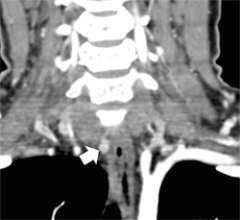

Figure 1a. Parathyroid 4D-CT showing a parathyroid adenoma in an abnormal position within the carotid sheath, missed during a prior surgery. CA= Carotid artery.

Figure 1b. Parathyroid 4D-CT showing a parathyroid adenoma in an abnormal position within the carotid sheath, missed during a prior surgery. CA= Carotid artery.